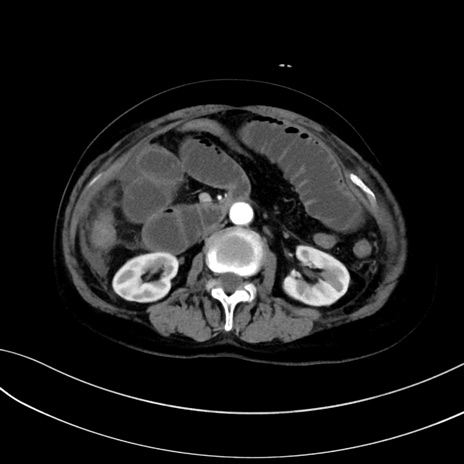

症例13 CT(横断像)1日半後